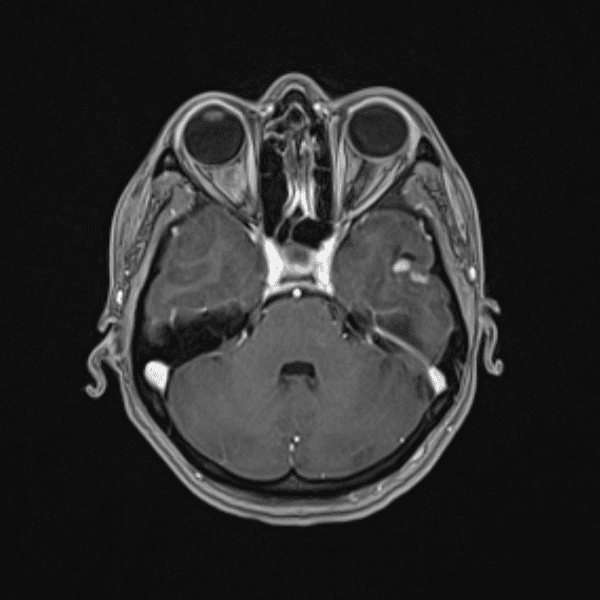

Classic Cases